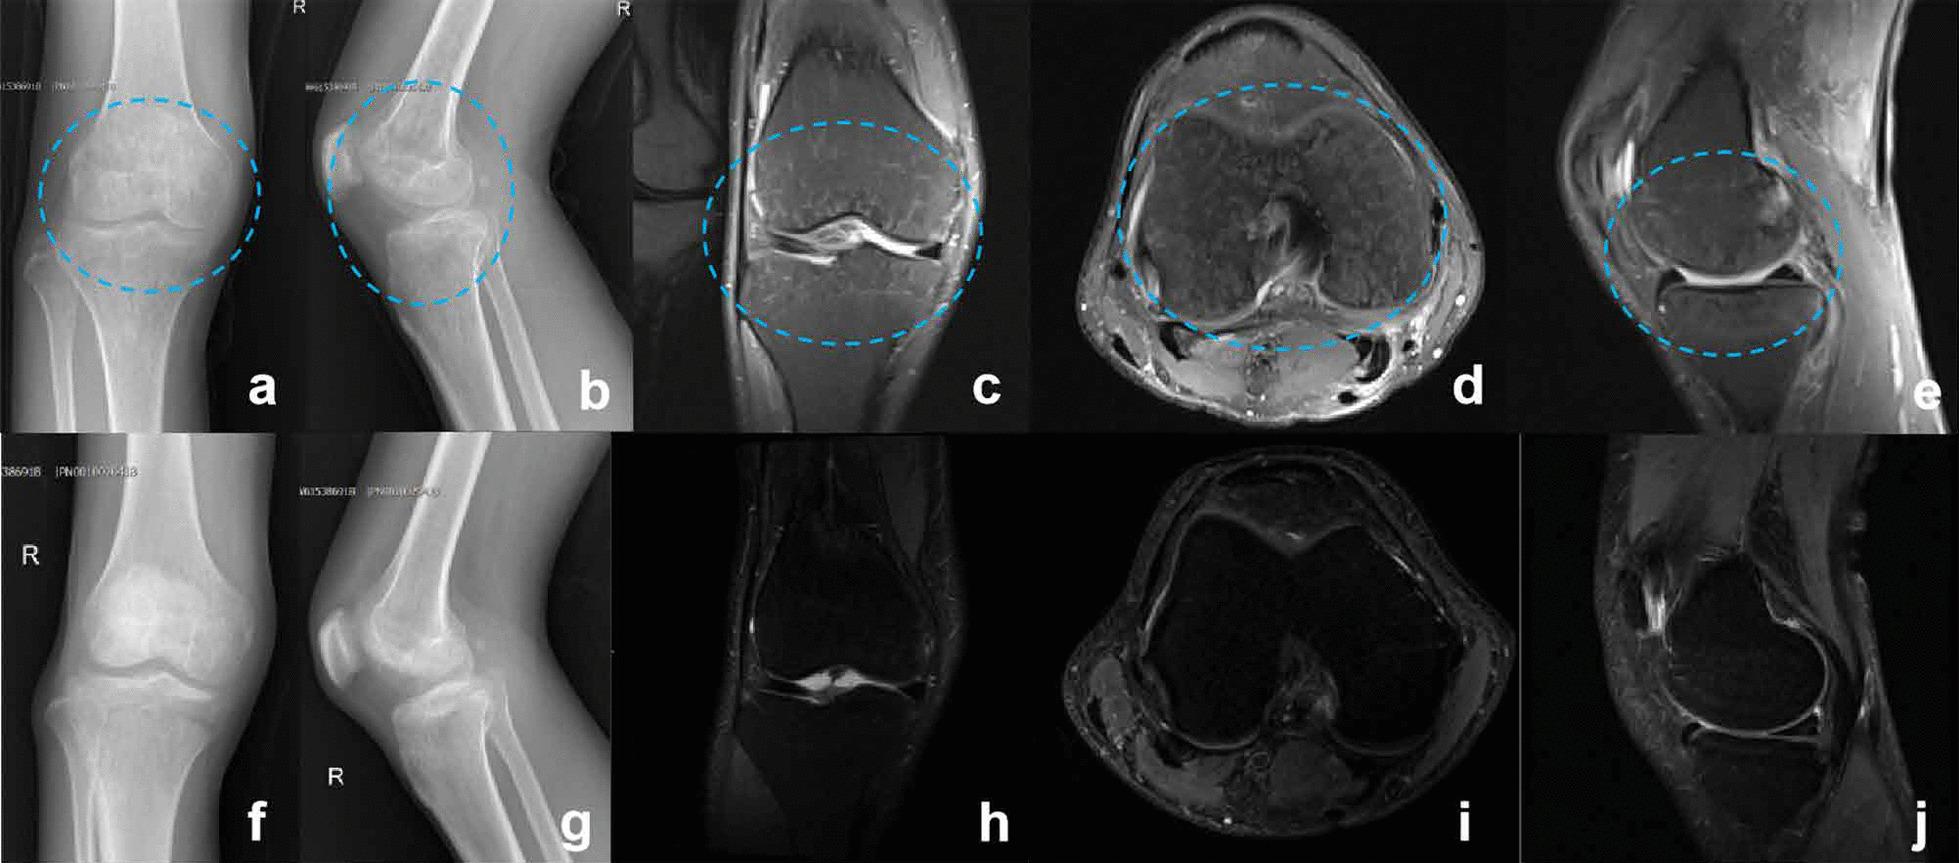

Both patients had a history of traveling in animal husbandry areas within three months. On clinical examination, their right knee joint was tender, swollen, had limited movement and an effusion was present. Imaging examination showed effusion and synovial thickening of the right knee joint, as well as subchondral bone edema of the distal femur and proximal tibia. Laboratory examination showed that the serum agglutination test (SAT) in both patients were positive (1: 640 and 1: 320) without leukocytosis, although the proportion of lymphocytes, erythrocyte sedimentation rate (ESR) and C-reactive protein (CRP) significantly increased. Both patients underwent knee joint aspiration. Real-time polymerase chain reaction (Real-time PCR) analysis of synovial fluid showed that there was B. melitensis, and blood bacterial culture was negative. We determined that two patients had acute brucellosis knee arthritis complicated by acute osteomyelitis. Antibiotic treatment was given during hospitalization consisting of doxycycline (0.1 g po bid) and rifampicin (0.6 g po qd) for six weeks, and the changes of inflammatory indexes were closely monitored. At discharge, the symptoms had completely resolved, imaging abnormalities disappeared, and inflammatory indexes returned to normal. There was no recurrence of the disease at 1-year follow-up.

两名患者均有 3 个月内到畜牧业地区旅行的病史。临床检查发现,他们的右膝关节压痛、肿胀、活动受限并伴有积液。影像学检查显示右膝关节积液和滑膜增厚,以及股骨远端和胫骨近端的骨软骨下骨水肿。实验室检查发现,两名患者的血清凝集试验(SAT)均为阳性(1:640 和 1:320),白细胞不高,但淋巴细胞比例、红细胞沉降率(ESR)和 C 反应蛋白(CRP)显著升高。两名患者均接受了膝关节抽吸术。关节液实时聚合酶链反应(Real-time PCR)分析显示存在马尔他布鲁氏菌,血培养阴性。我们诊断两名患者均患有急性布鲁氏菌性膝关节炎合并急性骨髓炎。住院期间给予多西环素(0.1 g 口服 bid)和利福平(0.6 g 口服 qd)治疗 6 周,并密切监测炎症指标的变化。出院时,症状完全缓解,影像学异常消失,炎症指标恢复正常。随访 1 年无疾病复发。